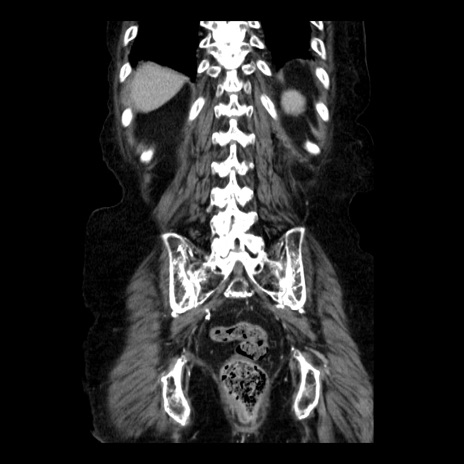

症例14(冠状断像)

【症例】 90歳代女性

【主訴】 腹痛・嘔吐

【現病歴】今朝から左側腹部痛を認めた。 経過観察していたが、嘔吐を認めたため来院。

【既往歴】 子宮癌術後

【身体所見】 意識清明、BP 127/54mmHg、P 98bpm Sp02 95%(RA)、BT 35.8°C、腹部平坦・軟腸ぜん動音聴取良好、右下腹部圧痛(+) 反跳痛なし

【データ】WBC 9800、CRP 0.46